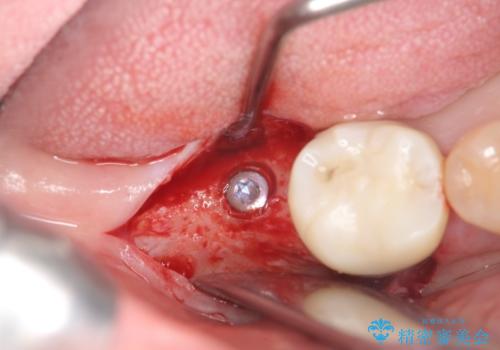

奥歯 インプラントによる機能回復

インプラントを用いて、しっかりとかめるような治療を計画します。

- 45万円(ストローマンインプラント・骨造成・チタンカスタムアバットメント・ジルコニアクラウン)費用は治療当時の料金となります

最後方臼歯はインプラントを用いることでしっかりと咬合機能を回復することができます。